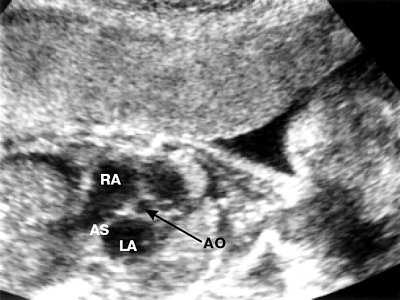

Межпредсердная перегородка значительно утолщена, наиболее это выражено в области овального окна (рис. 4), клапан которого закрыт (рис. 5). Поток крови через межпредсердную перегородку отсутствует.

Рис. 4. Четырехкамерное сечение сердца. Увеличение предсердий. Межпредсердная перегородка уплотена, овальное окно закрыто. Отмечено наличие выпота в брюшной полости.

LA - левое предсердие, RA - правое предсердие (стрелкой указана область овального окна, плотная по структуре).

Рис. 5. Сканирование поперечного сечения корня аорты.

АО - аорта, LA - левое предсердие, RA - правое предсердие, AS - межпредсердная перегородка.

Из анамнеза удалось выяснить, что беременная страдает герпетической инфекцией, обострение процесса наблюдалось во время беременности. По всей вероятности, инфекционный процесс послужил причиной преждеврменного закрытия овального окна.